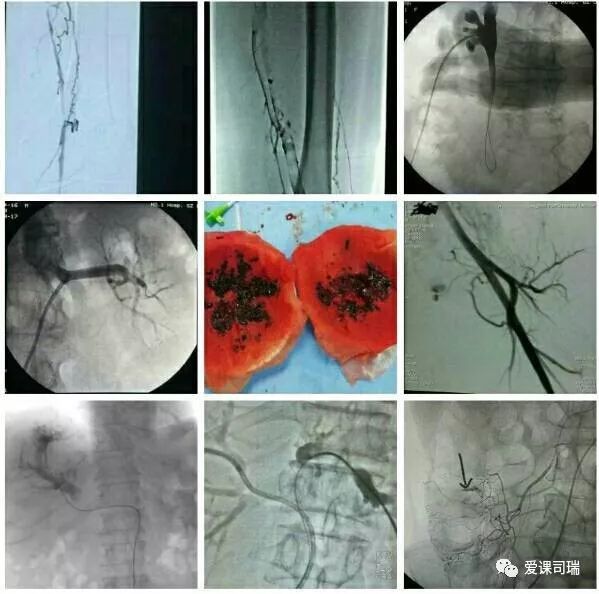

1.有影像设备的引导:在能够“看穿身体”的影像设备帮助下,不需要切开人体,就能看到体内脏器和病变,实现“可视化”。

3.诊断与治疗相融合:介入医生能够通过影像设备直接看到病变,疾病的诊断就很容易明确,随即又可立刻转入治疗过程,实现“诊断治疗一体化”或“诊治一条龙”。整个过程都看得见,治疗过程中又可继续诊断,如果判断效果还没有达到预期,立即追加治疗也非常方便。

概括地说,介入诊疗有以下优势: 1.可以远道施术:借助于导管等器材,可以从对病人最有利、远离病变的部位入手,将治疗器材送达病变局部,再施行精细的治疗。比如,头部有病,我们可以方便地从大腿跟部进管,经血管插管到头部去,从而避免直接切割或穿刺头部。 2.创伤轻微,容易耐受:借助于影像设备这“第三只眼睛”的引导,无须开刀即能清晰显示病变部位,从而进行准确的治疗操作。 3.可重复性强:由于创伤小,不会导致局部的粘连和策划缺损,因而可以多次反复地进行治疗,直到病变完全康复为止。 4.定位准确:有影像设备作实时的引导和监控,没有视觉盲区,因而可以“指哪打哪”。 5.疗效高、见效快:对很多病变可以起到“立竿见影”的效果。 6.并发症发生率低:也就是说安全性高,由上述多种优势的综合作用所致。 7.方便联合应用多种介入技术:介入诊疗技术种类繁多,各有特点和优势,可以方便地联合应用,取长补短,从而进一步增强治疗效果。

“介入”的应用范围涵盖了头颈、胸腹、四肢等各个部位,涉及神经、心血管、呼吸、消化、泌尿生殖、骨关节等各个系统器官的病变诊治。

介入放射学按诊治目的可分为介入诊断学和介入治疗学,按涉及学科可分为神经介入、心血管介入、肿瘤介入、妇产科介入等学科分支;介入诊疗技术按进入途径则可分为血管性和非血管性两大类介入技术。